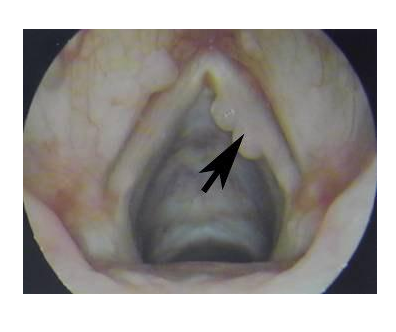

成人喉乳头状瘤

本病好发于50~60岁,为乳头状瘤病毒(HPV)感染引起。

乳头状瘤病毒已鉴定出60多种型别,HPV16 、18 、31 、33 型为高危病毒, 高危乳头状瘤病毒引起的喉乳头状瘤可开展为喉癌。